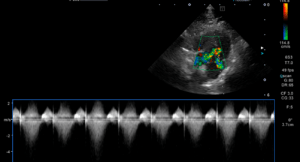

―心臓エコー検査:心筋の肥大、SAM(僧帽弁収縮期前方運動)、左心室内の肉柱を確認。

正常な猫の心筋は6mm以下と言われていますが 、今回の症例では最大6.9mmの肥大が認められました(上画像)。猫の肥大型心筋症は二股のジェット(ジェット気流が二股に分かれているように見える現象)が特徴です(下画像)。